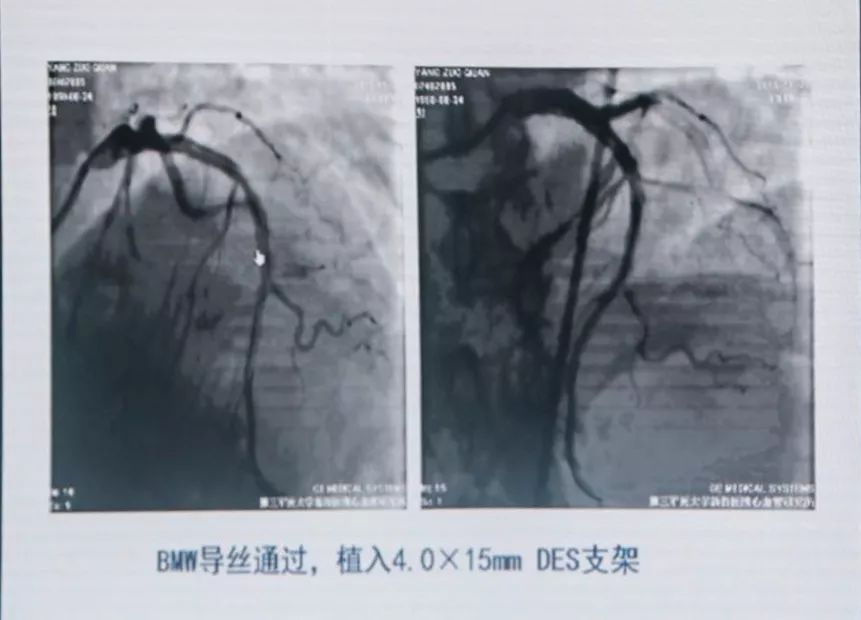

联系陆军军医大学第二附属医院胸痛中心,考虑亚急性支架内血栓形成,绕行急诊,PPCI。

分析血栓形成原因,可能是患者术后自行停用DAPT,支架贴壁不良等。

有条件者应尽快进入导管室行急诊冠状动脉造影,以多体位投照明确无夹层及支架膨胀不良。若血管完全闭塞,待球囊扩张部分血流恢复后再行造影。应尽快使导丝通过血栓病变,建议应用软头导引导丝。

支架内血栓形成可能与支架未充分贴壁有关。可用短于支架长度的高压球囊再次PTCA。若造影确认血栓形成可能与支架近或远端内膜撕裂、支架未完全覆盖病变有关,可再次置入支架,视察20 min后,若患者胸痛缓解、血压及心电监测稳定、TIMI血流III级,可视为成功。但应关注,除非有证据显示血栓形成与上述因素相关,否则不可再次置入新支架。Dutch研究发现,首次出现支架血栓的患者,再次置入新支架,发生支架血栓的风险比未置入新支架的患者增加4.2倍。